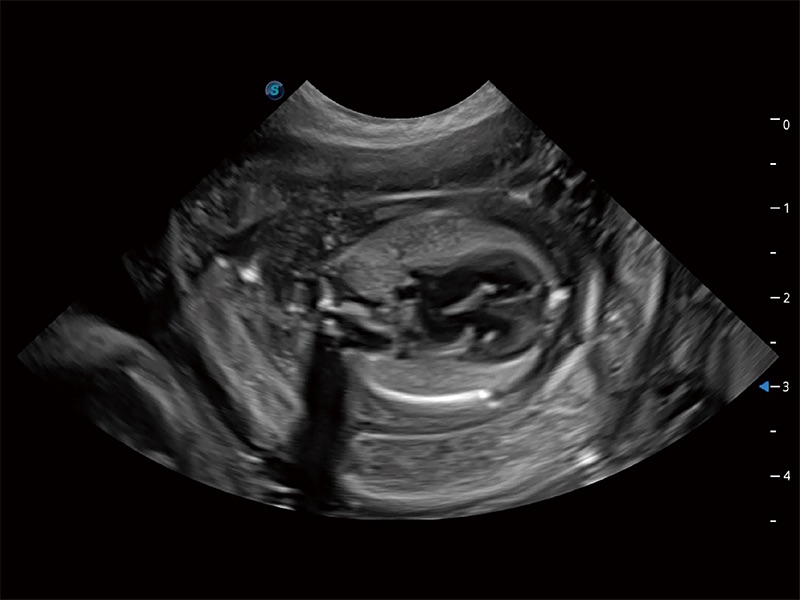

动物是人类最亲密的朋友和最值得信赖的伙伴。玖鼎集团也一直致力于探索动物专用的超声影像解决方案。全新推出的ProPet系列,是玖鼎集团在动物超声影像智能化、专业化、精准化的一次跨越式革新。动物不能用言语来表述自己的不适,通过超声影像,ProPet系列搭建了动物医生与不同物种沟通的“桥梁”,为动物医生注入了“治愈之力”。 ProPet 80 是玖鼎集团匠心打造的一款高端动物专用彩超,采用性能卓越的全新硬件架构,极大提升超声系统的运行效率和数据处理能力,帮助动物医生从容应对日益增多的挑战性病例和日益多样化的临床需求。

高性能和先进的临床应用工具可以为动物医生提供临床信心。ProPet 80 搭载了先进的腹部和浅表应用工具,帮助医生在日常临床实践中发挥前所未有的作用。

极大提升超低速微细血流的检出能力,同时更精准地滤除软组织和超声信号,为兽用医生提供以往无法通过常规血流获得的疾病诊断信息。

在传统二维血流成像的基础上,呈现血流的立体感,具有动感的生命力之美。即便是微小的血管也能轻松应对,提高了血流的视觉敏感性。